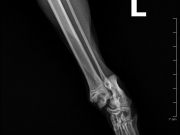

Į veterinarijos kliniką žmonės atvežė automobilio nutrenktą katinuką. Atlikus rentgeną paaiškėjo, kad abi užpakalinės kojos per sąnarius suknežintos į skeveldras. Vienos kojos raiščiai nutraukti. Apžiūrėjusi nuotraukas ir įvertinusi skeveldrinius lūžius chirurgė informavo kad operacija bus itin sudėtinga ir brangi. Vienu metu ji galėtų atlikti tik vienos kojytės operaciją, o po savaitės ar daugiau žiūrint kokia gyvūno būklė galės operuoti antrą. Visa tą laiką katinukas bus klinikos stacionare.

Chirurgė perspėjo kad operacija, gydymas ir pooperacine slauga klinikoje kainuos tikrai pakankamai daug nes užtruks mėnesį ar net daugiau laiko.